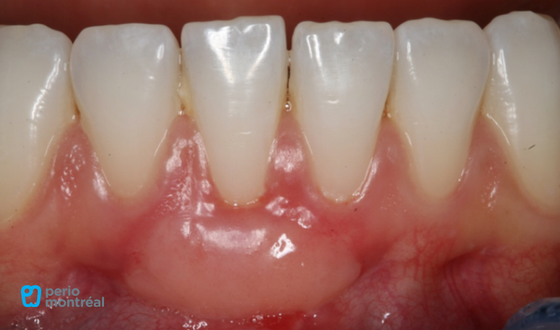

This patient “L.P.” presented with a chief complaint of “I bit in to a peach and caused this recession”. There is a Miller Class II recession defect on tooth #41 with a lack of keratinized tissue. The patient reports mild sensitivity to brushing.

- Miller Class II recession tooth #41

- Lack of keratinized tissue #41

- Mucogingival deformity associated with recession and a lack of keratinized tissue

- Mucogingival deformity #41